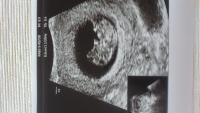

Kaptam egy fotót is,amit nem tudok feltölteni.... :oops:

Mégis sikerült! :-) Igaz kicsit furcsán... :lol:

Anne, jó a kép, annyira jó látni a babákat ilyenkor (is) :)

A méret is kimaradt, bocsi: 2, 89 cm :) ;) Óóóóóriáááási :D

Sziasztok! Tegnap voltam a kontroll uh.-és minden ok, hát sajna fotóm még nincs, de a lényeg hogy láthattam és végre szívhang is volt. Ma vagyok 9 hetes és a dátum május 11. :) És 24mm a kis drága. A következő már nekem is a 12 hetes uh. lesz, plusz hétfőn találkozás a védőnénivel. :)